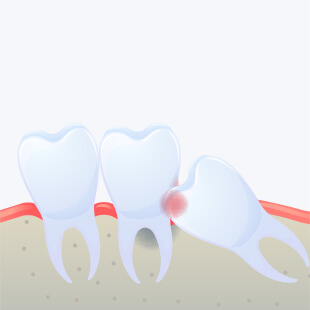

사랑니가 올바르게 자라나지 않고 삐뚤게 자라났거나 누워서 비스듬히 자라는 경우 옆 어금니를 손상시킬 수 있으며

또한 칫솔질이 잘 닿지 않는 부위이기 때문에 충치가 생기기 쉬워 이러한 경우에는 발치를 권장합니다.

염증을 유발할 수 있습니다.

사랑니가 누워서 나는 경우 치아와 잇몸사이 세균이 번식하기에 아주 좋은 환경이 되어 사랑니 주위염으로 발전할 수 있습니다.

사랑니가 삐뚤거나 누워 난 경우

사랑니가 삐뚤게 자랄경우 주변 치아를 밀어 치열을 불규칙하게 만들거나 뿌리를 압박해 염증과 같은 문제를 유발할 수 있습니다.